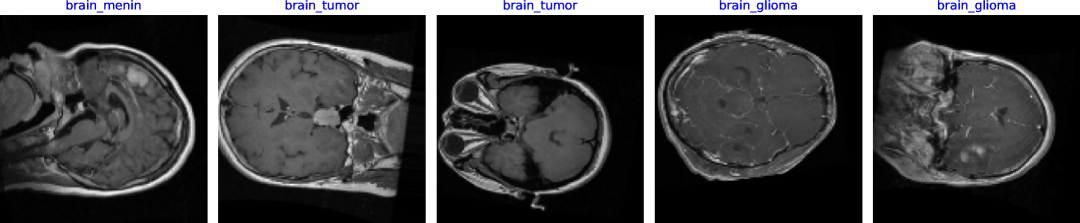

The dataset utilized for this investigation is the Bangladesh Brain Cancer MRI Dataset, a valuable resource for advancing brain cancer research through ML and DL techniques. It consists of 6,056 MRI images categorized into three classes: Brain Glioma (2,004 images), Brain Meningioma (2,004 images) and Brain Tumor (2,048 images), collected from various hospitals across Bangladesh to ensure a diverse and representative sample. Each image is resized to 512x512 pixels, making it compatible with a wide range of ML and DL algorithms. This dataset is essential for creating algorithms tailored to identifying and diagnosis of brain cancer within the Bangladeshi environment. The dataset is publicly available on Mendeley[13], facilitating further research in medical diagnostics. Figure 1 is showing some random samples of the dataset.

Refer to caption

Figure 1: Sample Images of the Brain Tumour Dataset